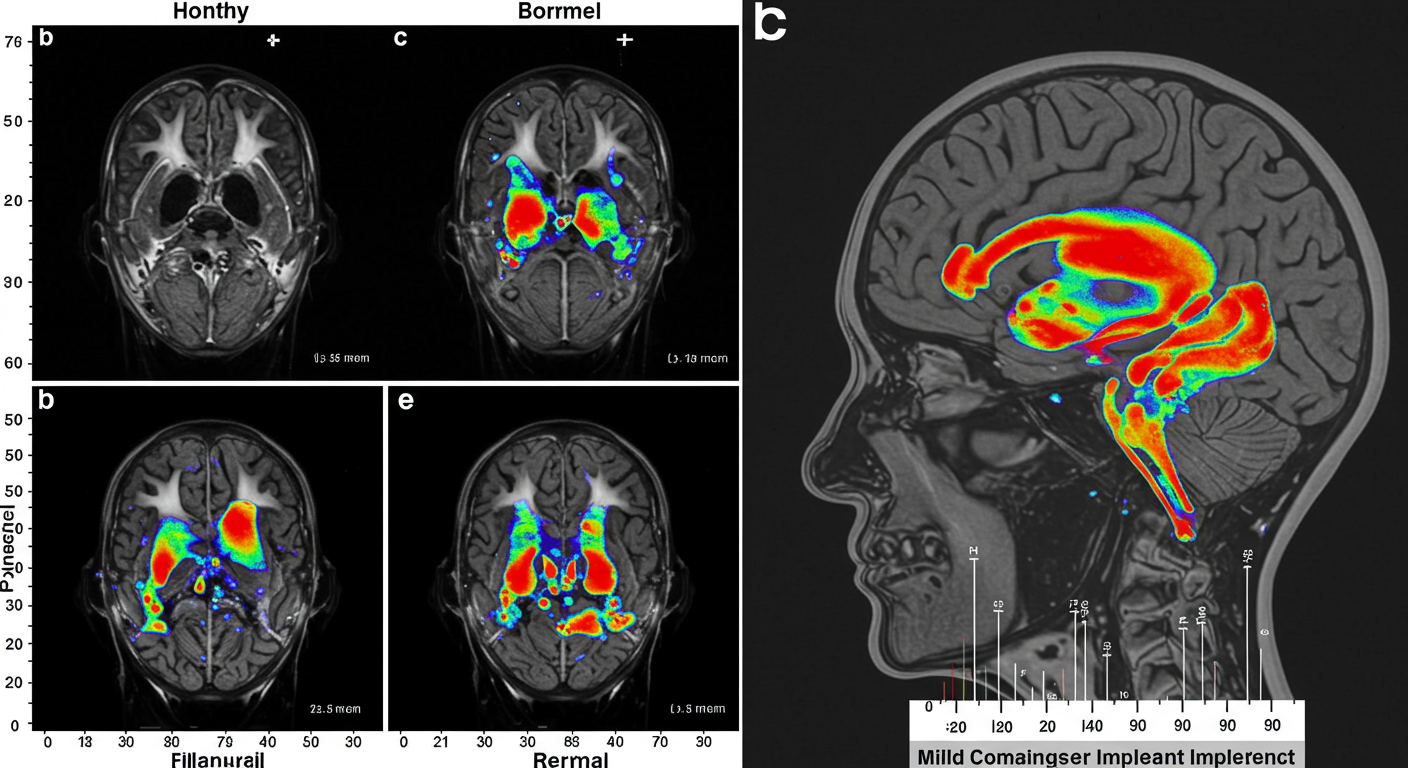

경도인지장애(MCI)의 실체와 중요성 💫

경도인지장애는 F067이라는 질병 코드가 부여된 의학적 상태입니다. 보건복지부의 실태조사에 따르면, 65세 이상 노인의 약 4명 중 1명이 이 단계를 겪고 있어요. 정말 높은 비율이죠! 😮

경도인지장애는 인지 기능은 분명히 저하되어 있지만, 아직 일상생활은 가능한 상태입니다. 말 그대로 정상과 치매 사이에 놓인 경계선이라고 볼 수 있어요.

경도인지장애는 크게 두 가지 유형으로 나뉩니다:

- 기억상실형 경도인지장애

- 주로 기억력 저하가 두드러짐

- 알츠하이머병으로 이행될 가능성이 높음

- 비기억상실형 경도인지장애

- 기억력보다 다른 인지기능의 저하가 두드러짐

- 이마관자엽치매나 혈관성 치매로 진행될 가능성이 높음